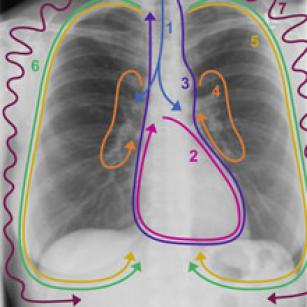

Medmastery’s chest x-ray algorithm—a systematic approach for evaluating any chest x-ray 21st Oct 2015 - Franz Wiesbauer, MD, MPH Learn to evaluate the chest x-ray according to our straight-forward algorithm and never miss an important problem ever ...

Getting into the chest x-ray—the importance of shapes and key landmarks (part 3) 16th Oct 2015 - Julian Dobranowski, MD, FRCPC In today’s teaching video you will learn how shapes and structures are formed on a chest x-ray.